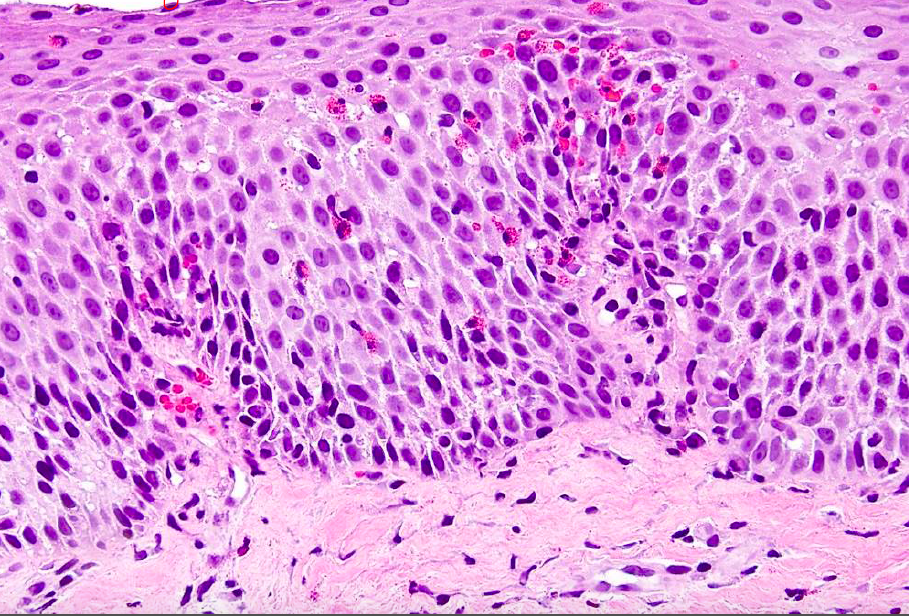

chronic colitis histo

distorted crypts

ulcerative colitis

diffuse predominatly mononuclear mucosal infiltrate

neutrophils in epithelium and in crypt

crypt abcesses

crohn histo

non caseating granulomas

acute bacterial campylobacter colitis

cryptitis/abcesses, mixed inflammation in lamina propria, no crypt distortion